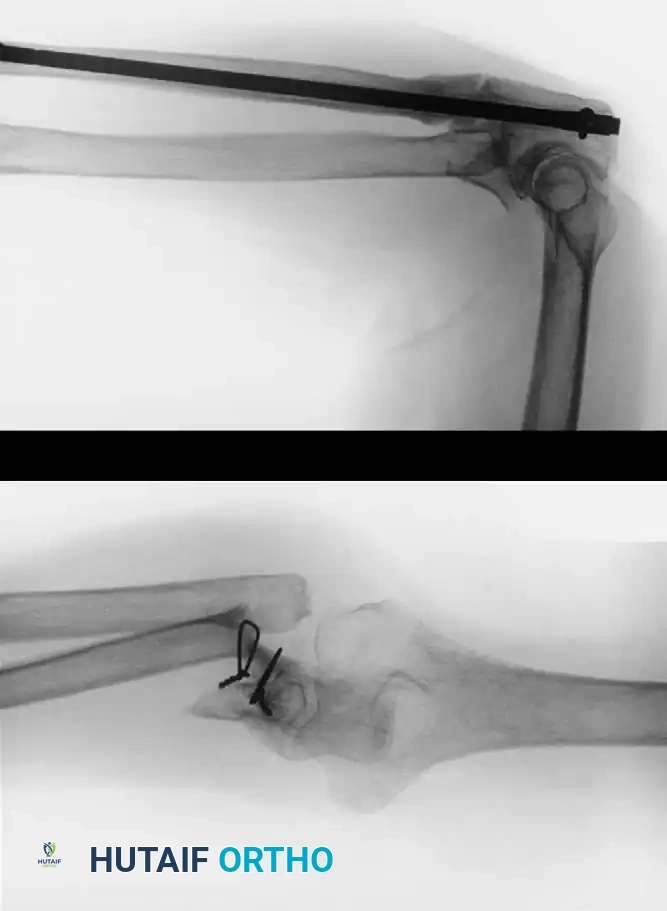

Fig. 56-18 Nonunion of medial malleolus treated by sliding graft.

Postoperative Protocol: A non-weight-bearing cast is applied from the toes to just distal to the knee. At 2 weeks, sutures are removed, and a walking cast or rigid boot is applied. Partial weight-bearing is allowed during the next 2 weeks, advancing to full weight-bearing thereafter. The immobilization is discarded when radiographs confirm osseous union, typically at 8 to 10 weeks.